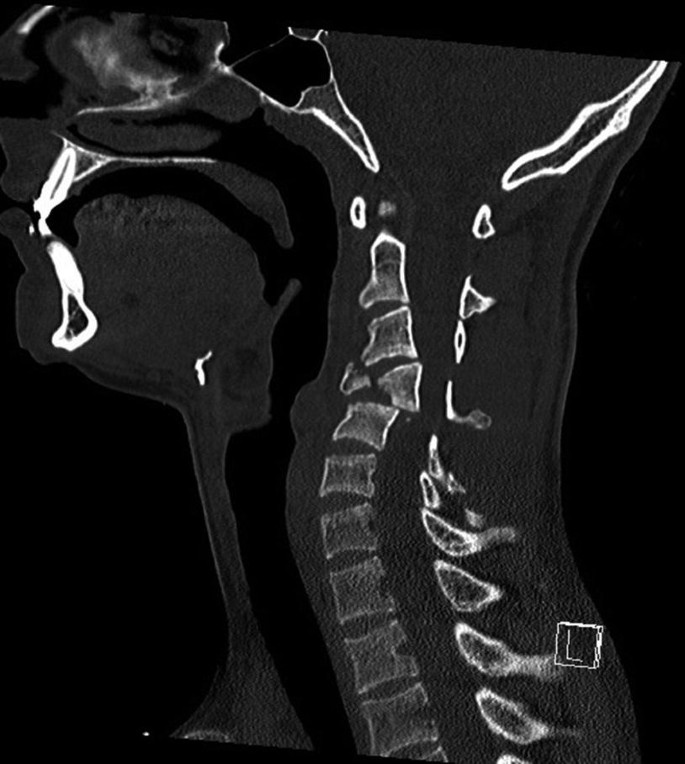

Cervical Spine Fracture Dislocation Springerlink